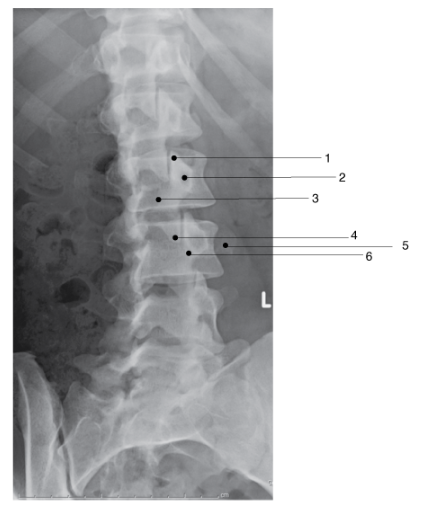

Which of the following is (are) well demonstrated in the lumbar spine shown in Figure 2–35?

C - 1 and 3 only

An oblique projection of the lumbar spine is shown. This is a 45-degree LPO projection demonstrating the zygapophyseal joints closest to the IR. The zygapophyseal joints are formed by the articulation of the inferior articular facets of one vertebra with the superior articular facets of the vertebra below. Note the “Scottie dog” images that appear in the oblique lumbar spine. Intervertebral foramina are best visualized in the lateral lumbar position

Which of the following is (are) well demonstrated in the lumbar spine pictured in Figure 2–8? 1. Zygapophyseal articulations 2. Intervertebral foramina 3. Pedicles A - 1 only B - 1 and 2 only C - 2 and 3 only D - 1, 2, and 3

C - 2 and 3 only A lateral projection of the lumbar spine is illustrated. The intervertebral articulations (disk spaces) are well demonstrated. Because the intervertebral foramina, which are formed by the pedicles, are 90 degrees to the midsagittal plane, they are also well demonstrated in the lateral projection. The articular facets, forming the zygapophyseal joints, lie 30 to 50 degrees to the midsagittal plane and are visualized in the oblique position. ``